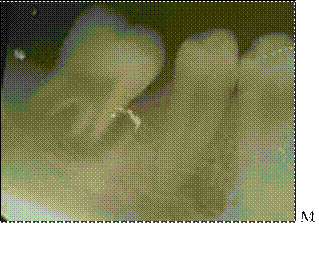

La figura J, se aprecia el plasma rico en plaquetas, en la figura K, implantación del tercer molar en el alveolo receptor y sutura. (Ver Anexo Figura 10).

Seguimiento postoperatorio Figura L, a la semana en la evaluación clínica Caso 2, se retiraron las suturas presenta una adecuada cicatrización de los tejidos. (Ver Anexo Figura 11)

Figura 9 J y K: Fotografías reales del caso 2. Utilización de PRF

Figura 10. Seguimiento postoperatorio estudio de caso 2